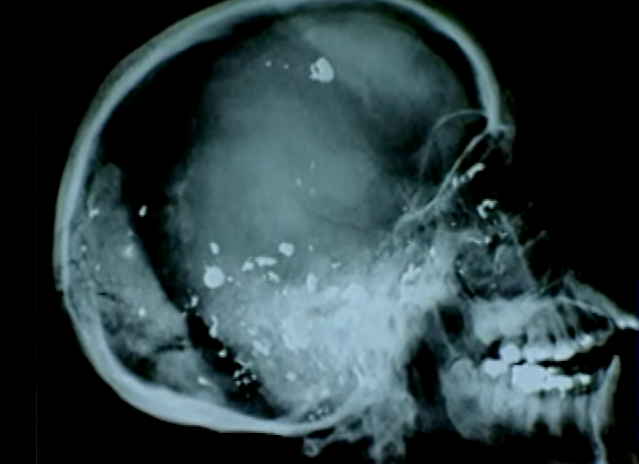

| Kết quả chụp X quang hộp sọ cho thấy nó có nhiều lỗ thủng và vết nứt, đồng thời chứa vài mảnh đạn - bằng chứng cho thấy ai đó đã bắn nạn nhân trước khi đốt xác. Chuyên gia pháp y đã mổ hộp sọ để lấy mảnh đạn. Hộp sọ vẫn còn chút máu, nhưng nhiệt độ của vụ cháy đã làm thay đổi toàn bộ thành phần hóa học của máu, khiến chuyên gia pháp y không thể phân tích DNA. Phổi nạn nhân không có khói, nghĩa là người này tử vong trước khi bị thiêu. |